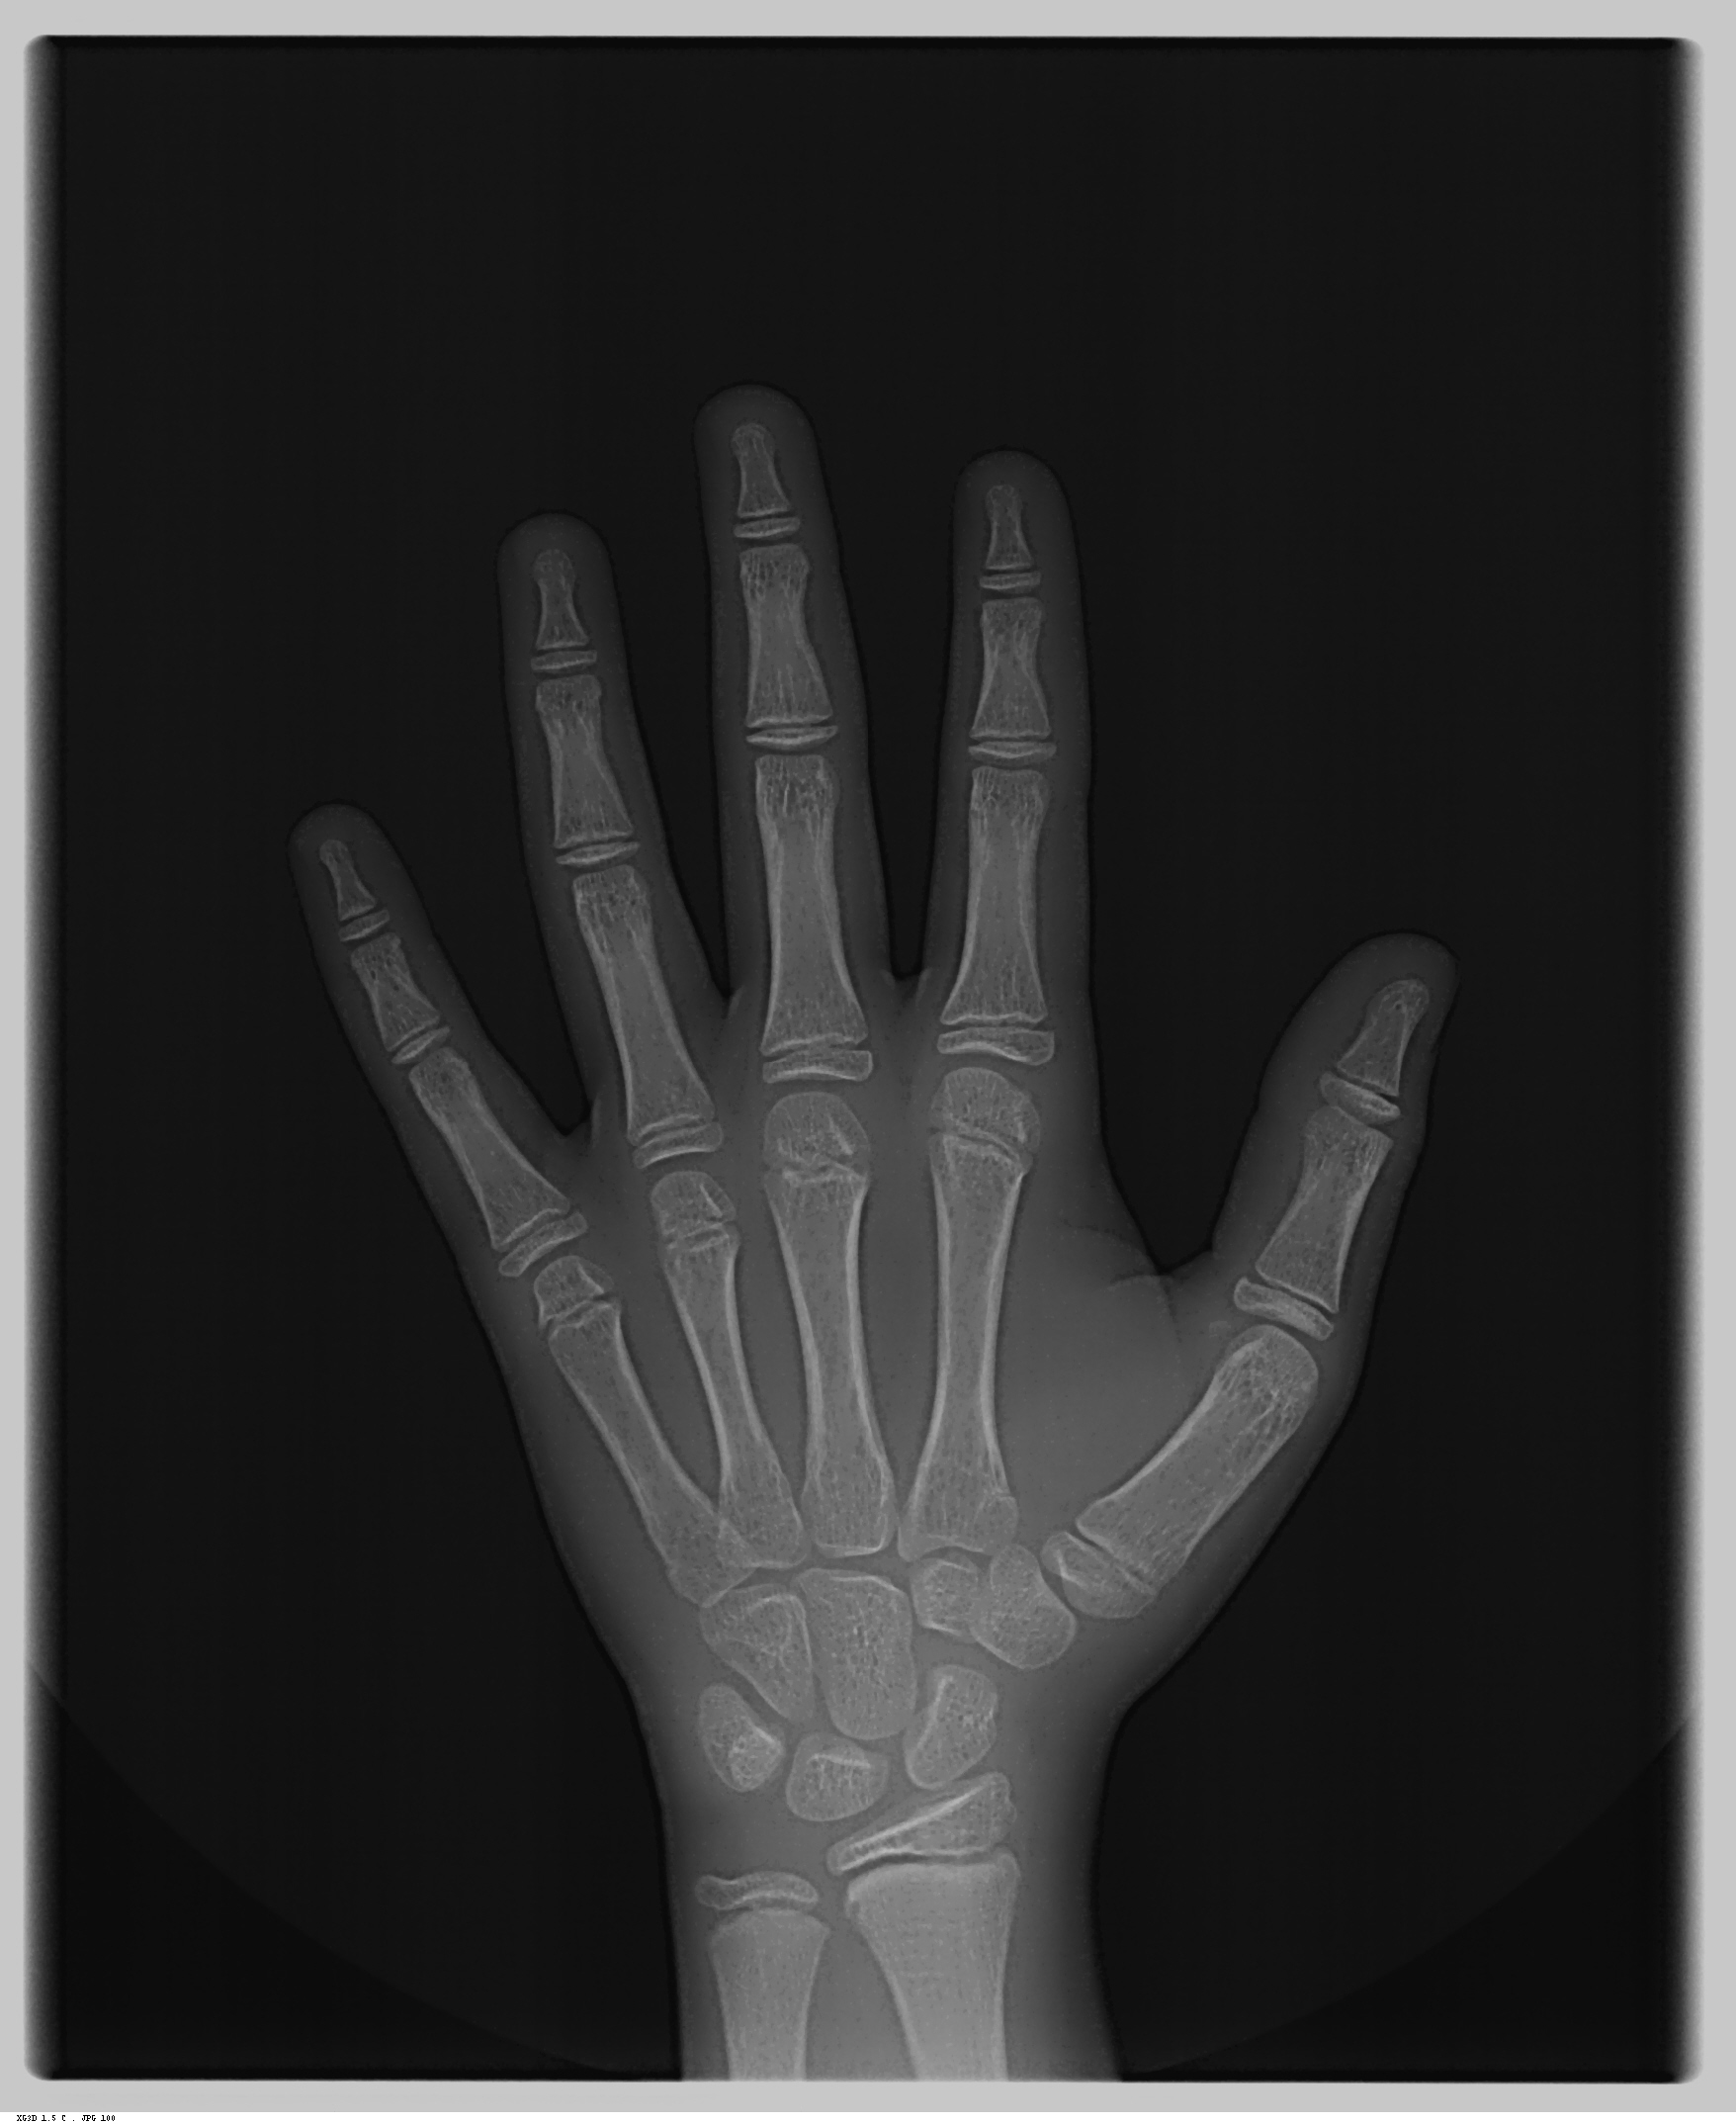

Carpal

É a radiografia da mão e do punho usada para a avaliação da idade óssea do paciente.